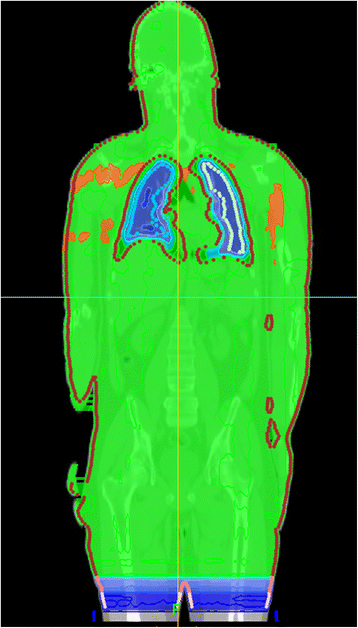

Background: The new TomoDirect™ modality offers a non-rotational option with discrete beam angles. We have investigated this mode for TBI with the intention to test the feasibility and to establish it as a clinical routine method. Special foci were directed onto treatment planning, dosimetric accuracy and practical aspects.

Results: For all eight calculated plans with a prescribed dose of 12 Gy Dmean was 12.09-12.33 Gy (12,25 ± 0.08 Gy), D98 11.2-11.6 Gy (11.45 ± 0.12 Gy) and D2 12.6-13.1 Gy (12.94 ± 0.13 Gy). Dmean of inner lungs was 8.73 ± 0.22 Gy on the left side and 8.69 ± 0.27 Gy on the right side. When single planning parameters are varied with otherwise constant parameters, the modulation factor showed the greatest impact on dose homogeneity and treatment time. The impact of the pitch was marginally, and almost equal homogeneity can be obtained with field width of Y-jaws 5 cm and 2.5 cm. Measurements with thermoluminescent rods (n = 25) in the Rando™ phantom showed a mean dose deviation between measured and calculated dose of 0.66 ± 2.26%. 18 of 25 TLDs had a deviation below 3%, seven of 25 TLDs between 3% and 5%.

Conclusion: TBI with TomoDirect™ allows a superior homogeneity compared to conventional methods, where lung blocks are widely accepted. The treatment is performed only in supine position and is robust and comfortable for the patient. TomoDirect™ allows the implementation of organ-specific dose prescriptions. So the discussion about the balance between the need for aggressive treatment and limited toxicity can be renewed with the new potentials of TomoDirect™ - for children as well as for adults - and possibly yield a better clinical outcome in the future.